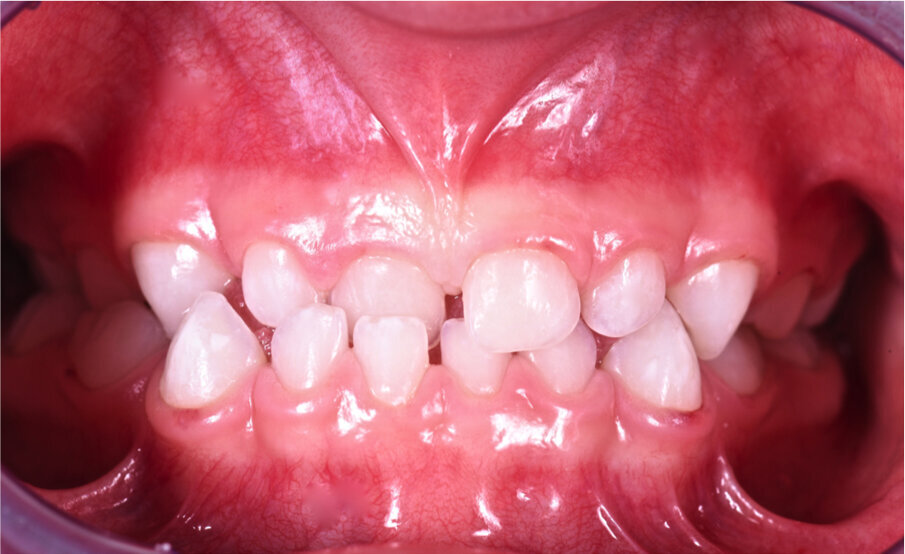

Caso 2 Paziente di anni 4, malocclusione dentale di III Classe, morso crociato monolaterale dx. La paziente viene trattata con dispositivo Amcop TC 2, il quale indossato tutte le notti e 1 ora di pomeriggio in 8 mesi risolve la malocclusione ripristinando il corretto rapporto occlusale; durante la terapia si riscontra un netto miglioramento della respirazione nasale e quindi il ripristino delle normali funzioni respiratorie. Il dispositivo, nei mesi successivi, viene indossato dalla paziente solo la notte per stabilizzare il caso e per guidare la crescita nel miglior modo possibile; all’età di 6 anni la paziente viene sottoposta a check-up ortodontico completo e quindi a panoramica e teleradiografia per poter analizzare anche la previsione di crescita e stabilire un eventuale step elastodontico (Figg. 15-23).

Fig. 15

Fig. 16

Fig. 17

Fig. 18

Fig. 19

Fig. 20

Fig. 21

Fig. 22

Fig. 23